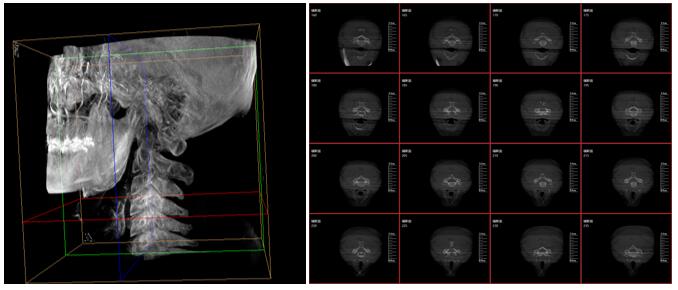

PLX7500三維成像圖片

這款新型三維C型臂—PLX7500集成手術(shù)導(dǎo)航和手術(shù)機(jī)器人接口,可無線傳輸三維重建的圖像數(shù)據(jù)至導(dǎo)航設(shè)備,無需額外手動注冊步驟,實(shí)現(xiàn)術(shù)中圖像的實(shí)時(shí)引導(dǎo)規(guī)劃,輔助醫(yī)生精準(zhǔn)定位手術(shù)器械和植入物,為實(shí)現(xiàn)手術(shù)室的數(shù)字化和智能化拓展提供可能。

采用30cmx30cm的動態(tài)平板探測器,輸出高分辨率、大尺寸的二維、三維圖像。超高16比特灰階度,高動態(tài)范圍清晰顯示植入物的位置和輪廓。

強(qiáng)大的圖像后處理功能軟件,自動調(diào)整比較好的圖像窗寬窗位,顯著降低螺釘?shù)慕饘賯斡?,降低圖像區(qū)域噪點(diǎn),進(jìn)一步優(yōu)化圖像品質(zhì)。